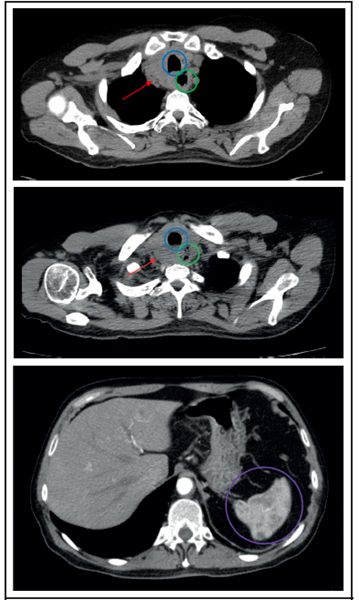

La tomografía computarizada con contraste (Figuras 1 A, B y C) mostró una masa sólida de 44x38 mm en el lóbulo tiroideo derecho que infiltraba la pared lateral del esófago y causaba estenosis de su lumen en un 80%, además demostró múltiples adenopatías cervicales en los grupos ganglionares II, IV y V bilaterales y adenopatías paratraquales inferiores. A nivel del parénquima pulmonar se observaron lesiones micronodulares de aspecto metastásico en ambos campos pulmonares. También se evidenció una fractura compresiva patológica a nivel del cuerpo vertebral T9 y una lesión nodular mal definida en el bazo, posiblemente metastásica.